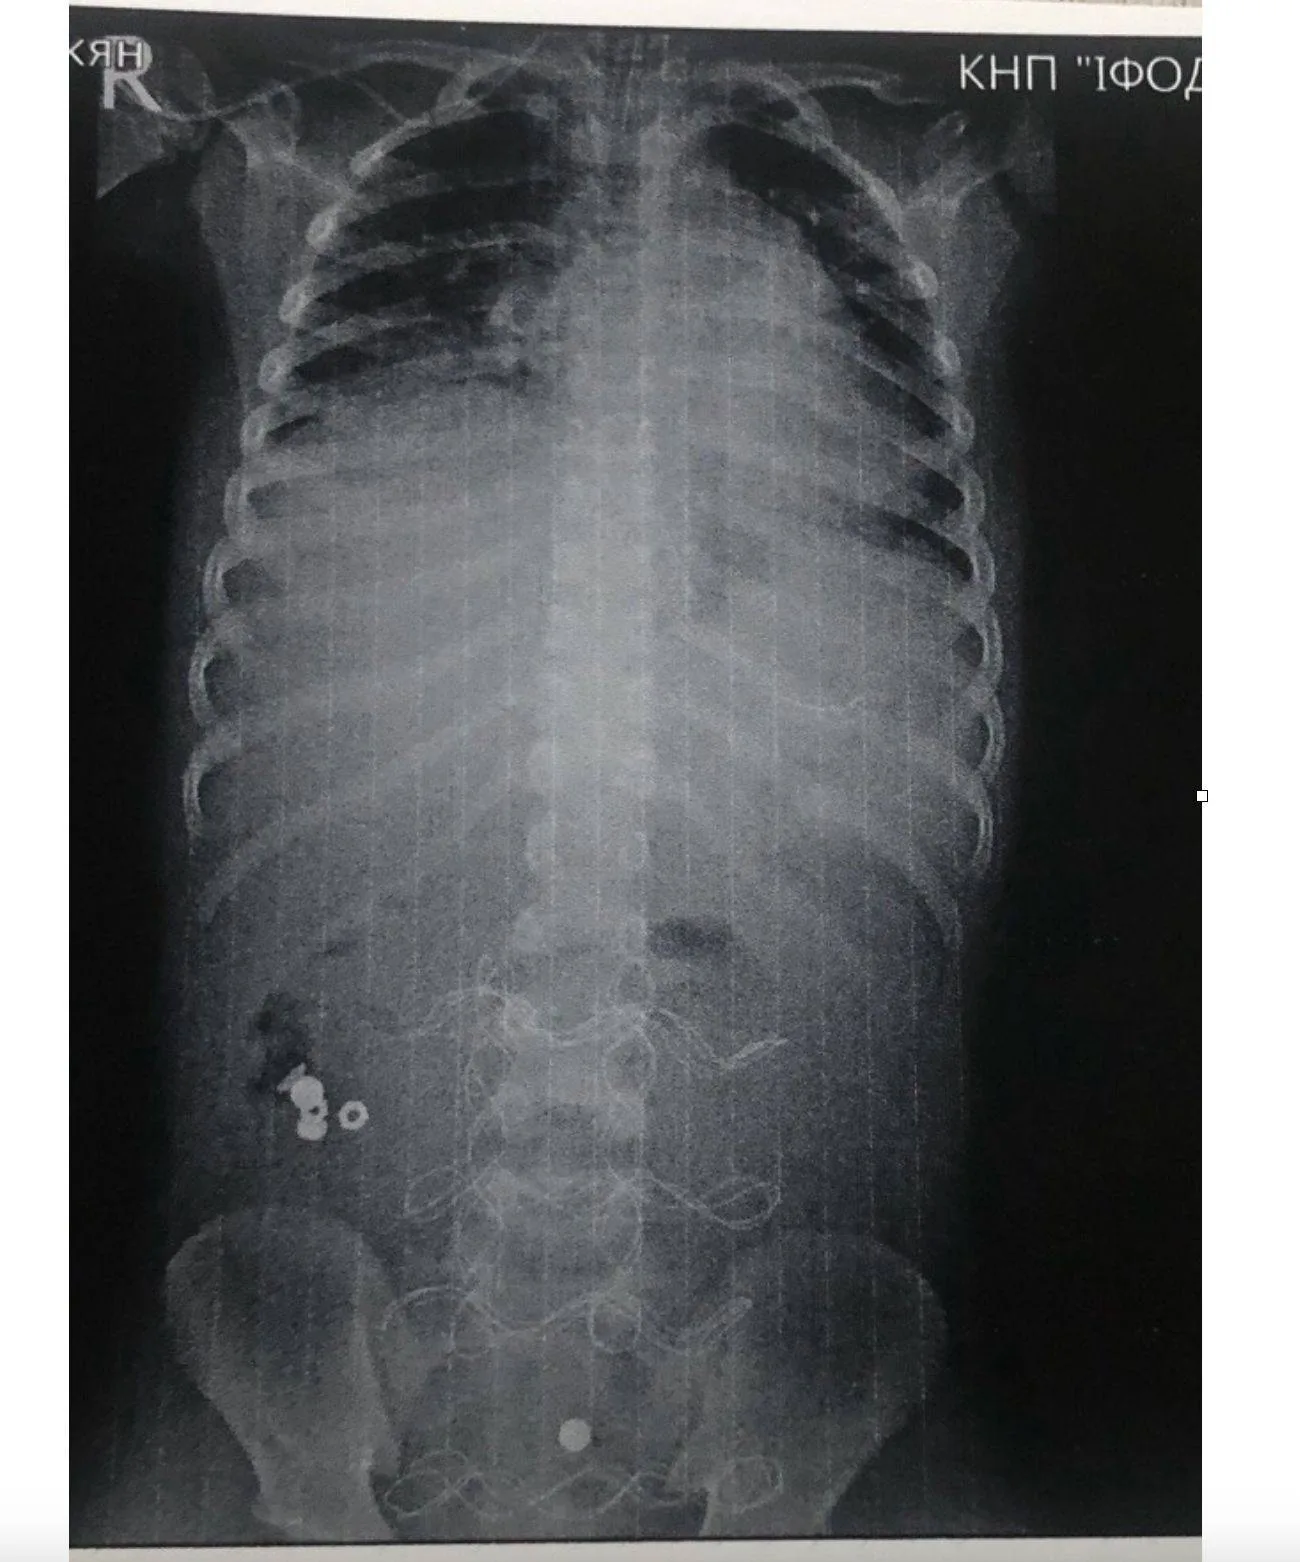

До Івано-Франківської обласної дитячої клінічної лікарні привезли 7-річного хлопчика в стані інфекційно-токсичного шоку з ознаками розлитого перитоніту. Як з’ясували лікарі, причиною стало проковтування батарейки, яка спричинила перфорацію тонкого кишківника.

Передопераційна підготовка тривала 12 годин. Загалом медики провели три оперативних втручань, доклавши максимум зусиль для стабілізації стану дитини.